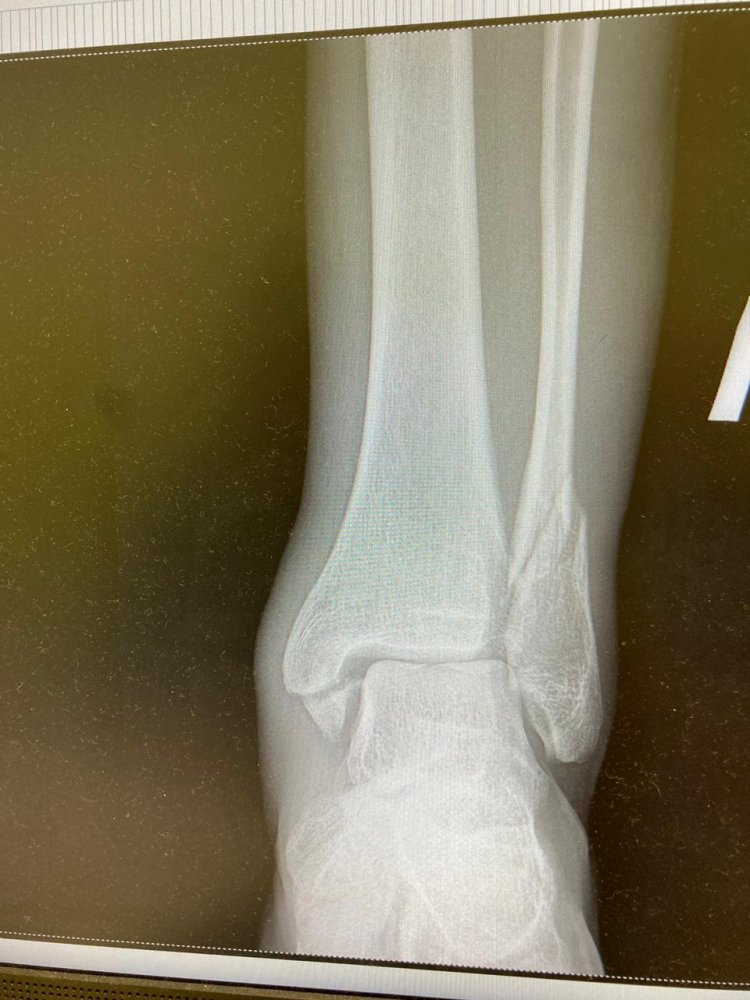

Саш,посмотри пожалуйста снимки

Операция обязательна?

А то завтра хотят резать и пластины ставить

{$title} {$title} {$title}

Димон, фиксировать лодыжку надо обязательно. Гипс - херня...он после операции пойдет...или жесткий ортез.

Перелом лодыжек -самое г...но. ..при неправильном сращении чел всю остатнюю жизнь хромать будет....как и при порванных связках г/стопа. Сустав сложный, должен вращаться во всех направлениях

Лодыжки целые Саш

При ударе об борт нога в суставе вывернулась градудосов на 130 этим и отломала кусок большой берцовой,а малая берцовая тоже как то сломалась,то ли от этого же то ли от удара

Сказали что в понедельник очень хороший врач будет оперировать меня и титан с болтами будет качественный-швейцарский))

Даже 5 см от конца кости - все равно перелом лодыжки называется

Металл хороший важен...и там титан, и тут, а результаты и осложнения разные

Без преувеличения...полгода костыликом от баб будешь отмахиваться...главное, оччень не торопясь восстанавливаться

В твоем возрасте среднее время сращения 30 -35 дней...а дальше реабилитация